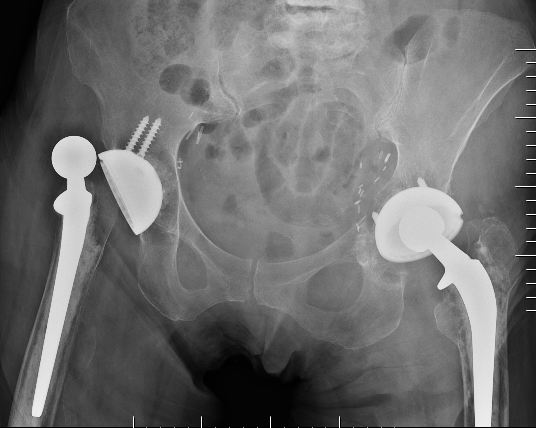

Recurrent THA dislocation evaluation

Evaluation

Acetabular inclination

Acetabular version

Femoral version

Offset / LLD